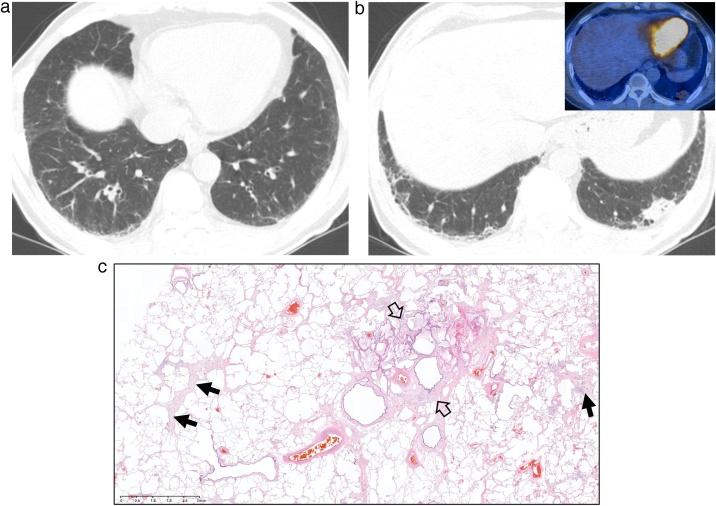

Interstitial lung abnormality (ILA) and nonspecific interstitial pneumonia (NSIP).

This review article aims to address mysteries existing between Interstitial Lung Abnormality (ILA) and Nonspecific Interstitial Pneumonia (NSIP). The concept and definition of ILA are based upon CT scans from multiple large-scale cohort studies, whereas the concept and definition of NSIP originally derived from pathology with evolution to multi-disciplinary diagnosis. NSIP is the diagnosis as Interstitial Lung Disease (ILD) with clinical significance, whereas only a part of subjects with ILA have clinically significant ILD. Eventually, both ILA and NSIP must be understood in the context of chronic fibrosing ILD and progressive ILD, which remains to be further investigated.